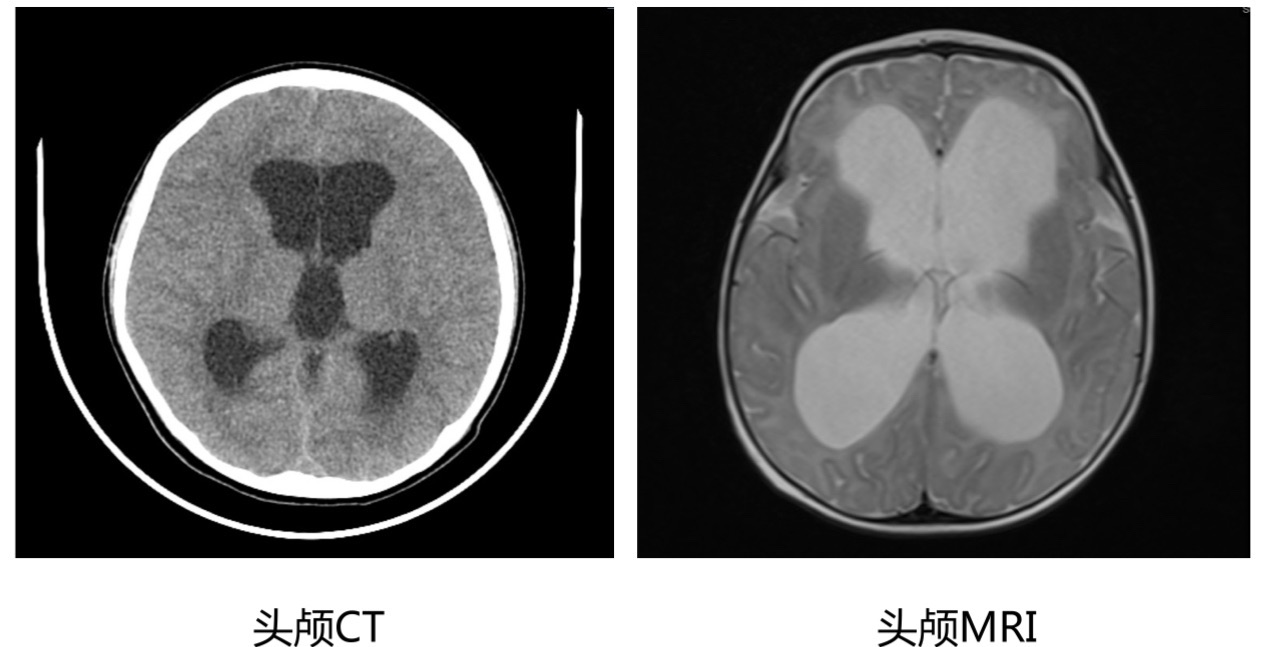

脑积水的宝宝会有哪些表现呢? 脑积水的表现主要取决于发病时间(相对于颅缝闭合的时间)、颅内压增高的速度及持续时间以及是否伴有相关的结构异常。 1. 婴儿和儿童轻度脑积水可能没有症状,通常是偶然检查发现的; 2. 颅缝闭合前的脑积水宝宝:最常见的表现就是头围增大,也就是前面提到的“大头娃娃”,头太大,颈部肌肉比较薄弱,以至于出现抬头不稳或者不能抬头,与同龄宝宝相比,有可能存在发育迟缓,比如说到了该抬头的月份不能抬头、不能翻身、不能坐起、不能站立等等,有些宝宝甚至还会出现发育倒退、行为改变,比如容易激惹等; 3. 年龄较大的儿童:因为颅缝闭合了,少了颅缝和囟门能够缓冲的空间,所以脑积水多的情况下,会出现明显的颅内压增高的表现,包括清晨头痛明显、恶心、呕吐、行走不稳、行为改变等等; 4. 急性脑积水:除了头痛、呕吐,还可能会出现意识状态的改变,包括昏睡、嗜睡等; 5. 外观上的异常:婴幼儿的脑积水比较容易从外观上发现,包括头围增大,头皮静脉很明显、曲张或者显露、囟门张力高、“落日征”(眼睛不能上视,总是下翻,露出眼白部分)等。 怀疑脑积水应该做哪些检查呢? 1. 定期监测头围:如果婴儿在孕期产检有脑室增宽、出生时有头围增大,连续监测头围的测量值总是在标准曲线以上,表明头部生长过度,应怀疑婴儿有脑积水,要做进一步的检查。 2. 颅腔B超:对于新生儿和小婴儿,即前囟还没有闭合的宝宝,可以选择做个颅腔B超,非常便捷,一般不需要镇静。 3. 头颅CT或者头颅MRI:对于疑似脑积水的年龄较大的婴儿和儿童,应该进行头颅CT或者头颅MRI检查,除了评估脑积水的程度,还可以发现结构异常或者肿瘤等后天因素。 4. 眼底检查评估视乳头水肿:脑积水引起颅压增高还会导致视乳头水肿、视物不清楚、视力下降等情况,对于脑积水的年龄较大的儿童,可以做眼底检查评估是否存在视乳头水肿,也可以侧面反应脑积水导致颅压增高的情况。

脑积水头颅CT和MRI的影像学表现